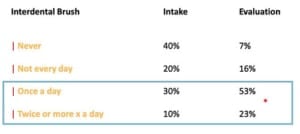

De richtlijn van de NVvP richt zich met betrekking tot stap 1 op de inventarisatie van het niveau van zelfzorg, het begeleiden en optimaliseren van mondhygiëne en gedragsverandering. Het advies is om 2x per dag te poetsen met fluoridetandpasta. Patiënten willen vaak weten wat ze moeten doen, maar doen het vaak niet omdat motivatie vaak het probleem is.

Stap 4 bestaat uit nazorg waarbij eerst de situatie wordt beoordeeld. Het is ook belangrijk dat de patiënt zelf zorgt voor supragingivale plaquecontrole door middel van het begeleiden van de patiënt met het gebruik van een elektrische tandenborstel en cilindrische ragers. Het bijsturen van de motivatie en instructie is een belangrijk onderdeel van de nazorgbehandeling. Uiteraard wordt er een professionele gebitsreiniging uitgevoerd, sub en supragingivaal. Bloeding na sonderen is daarvoor een belangrijke parameter. Uiteindelijk voor een nazorg behandeling afgerond met polijsten en op inidctaie het aanbrengen van fluoride. Ten slotte wordt een recall interval wordt bepaald tussen 3 en 12 maanden. Belangrijke factoren om dit interval te bepalen zijn roken, diabetes, aantal pockets > 5 mm, BOP% en hoeveelheid botverlies. Om deze stappen binnen de nazorg goed te kunnen doorlopen en voldoende tijd te kunnen besteden aan alle aspecten is het zo genoemde “profy hour” bedacht.